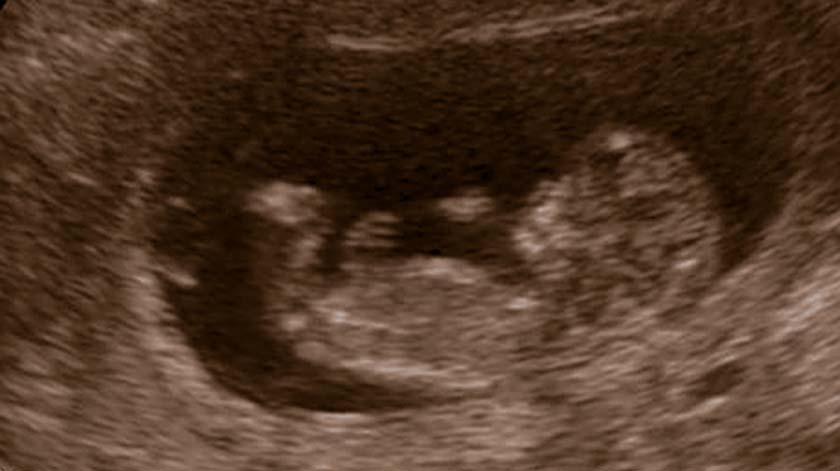

Foto: © Henk-Jan Oudenampsen